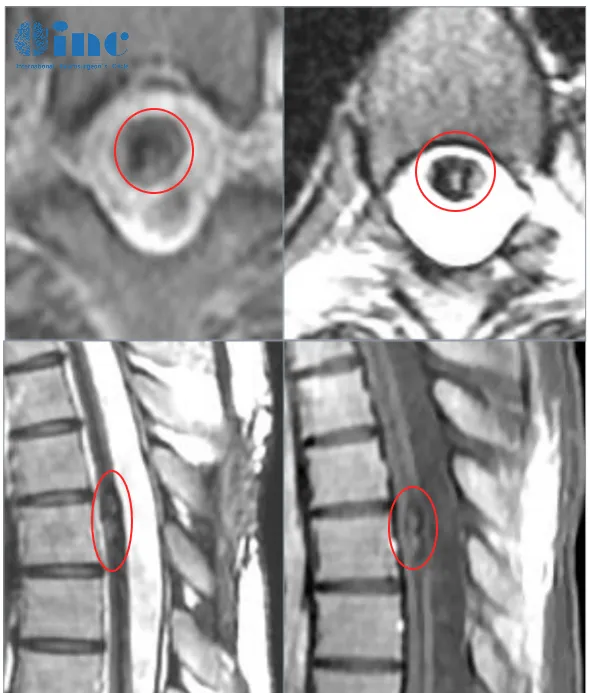

患者田田是一名21岁的在校女大学生,在一次参加完常规体育运动后自感后背轻微疼痛,两天后出现双下肢无力,检查诊断胸髓髓内出血性病变。

后续病情进展很快,还出现小便困难,双下肢无力加重等症状。再次检查后确诊胸髓髓内6海绵状血管瘤,医生考虑血管瘤位置比较深,在腹侧,手术风险大,做完肯定会瘫痪,建议保守治疗。再次出血,两天内症状急剧加重,双下肢运动功能丧失,大小便失禁。